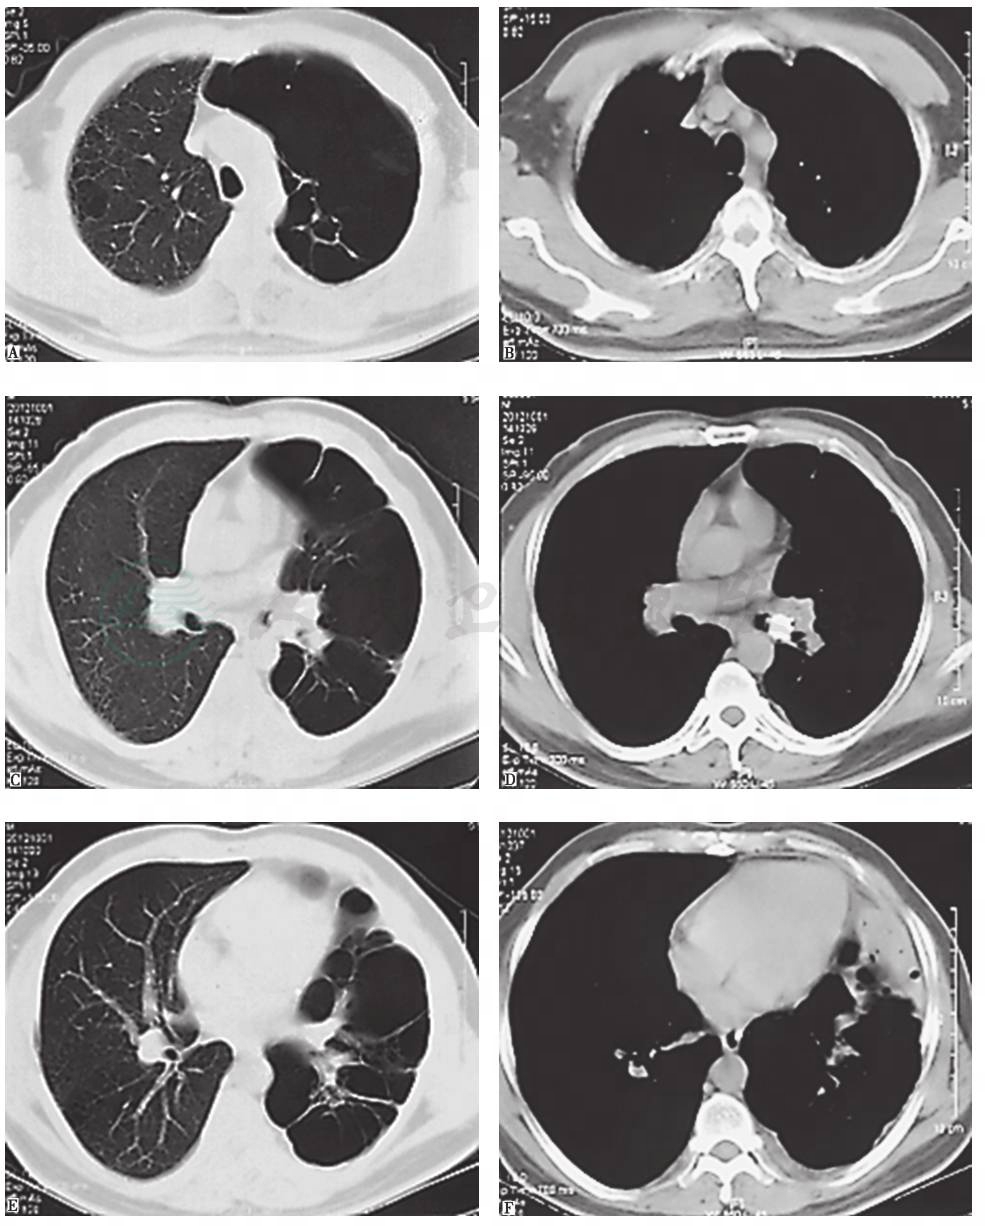

入院1个月前,胸部CT见左侧多发肺大疱,左下肺脓肿,其内见液平,左主支气管腔内高密度影,左侧少量胸腔积液(图1),抗感染治疗后未见好转(图2)。

图1 1个月前胸部CT表现

4.影像学检查显示左肺过度充气,多发肺大疱,其内可见气液平,左主支气管腔内可见钙质密度占位影。